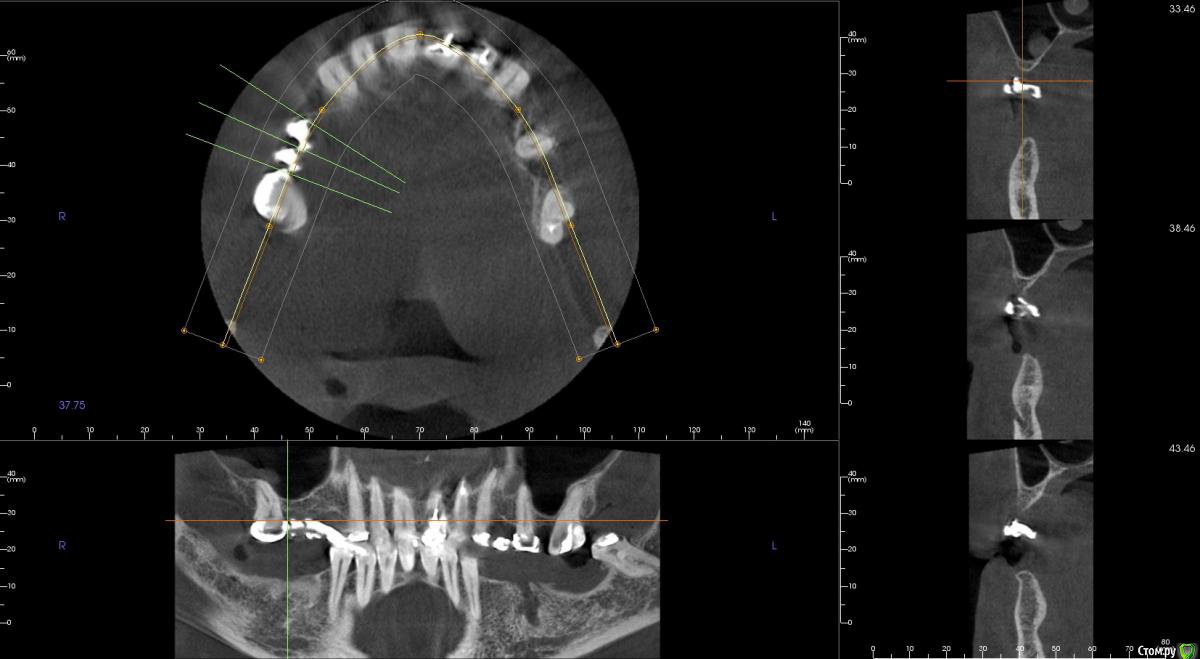

kamranchick Опубликовано 8 февраля, 2017 Автор Поделиться Опубликовано 8 февраля, 2017 Спасибо за публикацию.Какова ширина гребня?5мм сверху в области кристального модуля имплантата дальше около 7мм) Ссылка на комментарий